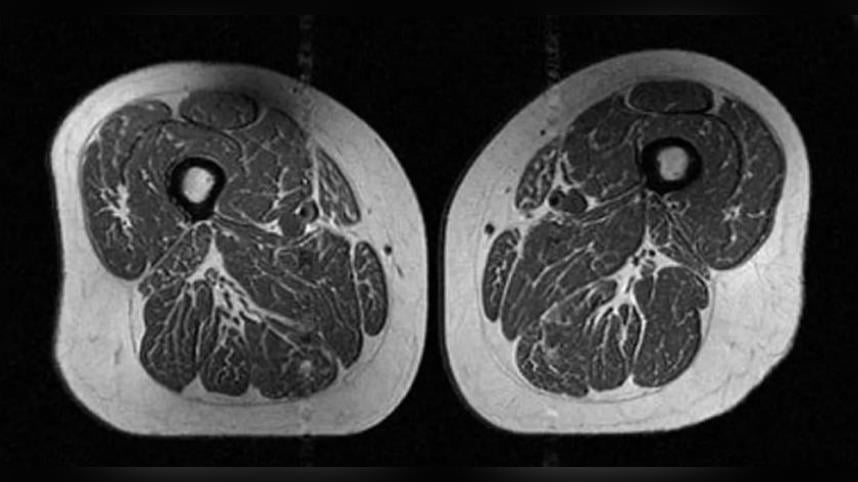

蔡明劼PO出研究中的核磁共振影像,照片中比較2名BMI相近的女性,左圖的女性,攝取超加工食品佔一天總熱量的29.5%;右圖的女性則攝取87.1%,「儘管兩者的BMI相近,腰圍以及大腿油花指數竟然有天壤之別」。

蔡明劼表示,這種現象在男女身上都一樣明顯,代表攝取超加工食品會導致肌肉品質下降。蔡明劼說明,大腿肌肉功能對於膝關節的穩定性至關重要,一旦肌肉品質被脂肪取代,支撐力就會下降,導致肌力衰退、走路速度變慢,進而影響整體的活動能力,還可能引發發炎反應及功能性影響,進一步損害關節健康。另外,研究也發現,考量到反映內臟脂肪分布的中央型肥胖,腰圍與大腿肌肉脂肪的關聯性比看BMI更明顯。